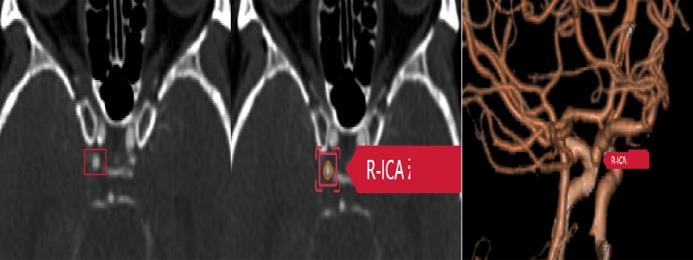

What is your diagnosis for a patient who presents with increasing size of neck and shoulder region?